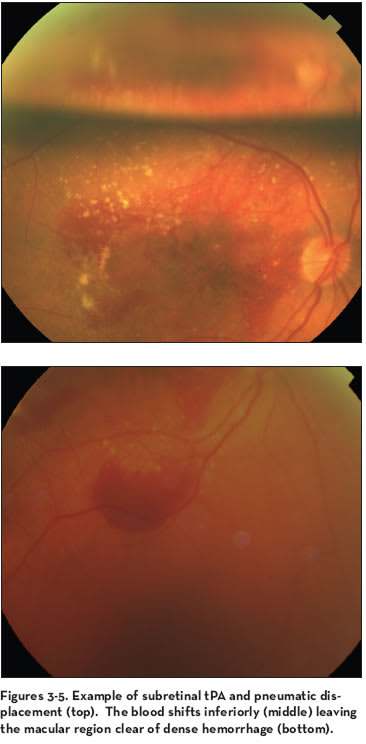

Creation of the Subretinal Bleb

An augmentation to the pneumatic displacement with intravitreal gas is the addition of a subretinal bleb of tPA. This technique, described by Haupert and colleagues,21 involves a vitrectomy with subretinal injection of 25 μg/0.1 mL using a 36-g cannula, without manipulation of the clot. The concept of the tPA bleb is that a limited, controlled retinal detachment will provide room for the fibrin in the clot to disengage from the photoreceptors without excessive trauma and float downward in a fluid mixture with the force of the gas tamponade and face-down positioning. This concept was derived from the macular translocation work where subretinal blebs are used to detach the retina.

The patient underwent a pars plana vitrectomy (PPV) and creation of a hyaloid detachment. A location was selected to infuse the tPA for the retinal bleb. This was usually superior to the submacular hemorrhage. Vessels were avoided. A bullous retinal detachment was created by infusing tPA with the smallest bore cannula available. Approximately 0.1 to 0.2 mL was used for a total subretinal tPA dose of 100 μg (not milligrams).

Care was taken to avoid injection into the choroids. No laser was used around the small entry-site retinotomy. Without any waiting period, an air fluid-gas exchange was performed with gentle aspiration at the disc without any attempt to evacuate the blood. The eye was filled with nonexpansive, short-acting gas, sulfur hexafluoride (SF6). The patients were placed face down as soon as possible so that the fluid and clot would shift inferiorly.

All patients demonstrated displacement of the hemorrhage outside of the fovea. Nine of 11 patients in their series had VA improvement. Subsequent recurrence of hemorrhage occurred in 27% of the patients. This series, published in 2001, was well before the anti-VEGF medication era.

For another patient with vision loss to count fingers with a fresh submacular hemorrhage, like the patient described above, the technique of the tPA subretinal bleb with pneumatic displacement was chosen. In this case, approximately 0.2 mL of tPA (concentration 12.5 μg/0.1 mL) was infused through a flexible small-tip cannula. The location of the retinotomy site was chosen superior to the hemorrhage. Certainly, anti-VEGF medication could have been used prior to surgery, but vitrectomy would wash out some unknown portion of the medicine. It could have been given at the end of the case as well. It was decided in this case to see whether the neovascular complex would be active after the blood was cleared without the addition of anti-VEGF.

The blood shifted inferiorly leaving the macular region clear of dense hemorrhage. A fluoroscein angiogram was performed 1 week after displacement, which revealed no treatable CNV lesion. Yet, after several weeks, a new occult lesion was seen and intravitreal anti-VEGF medication was used. The vision stabilized to the 20/200 level and still requires close observation and maintenance with anti- VEGF medication.